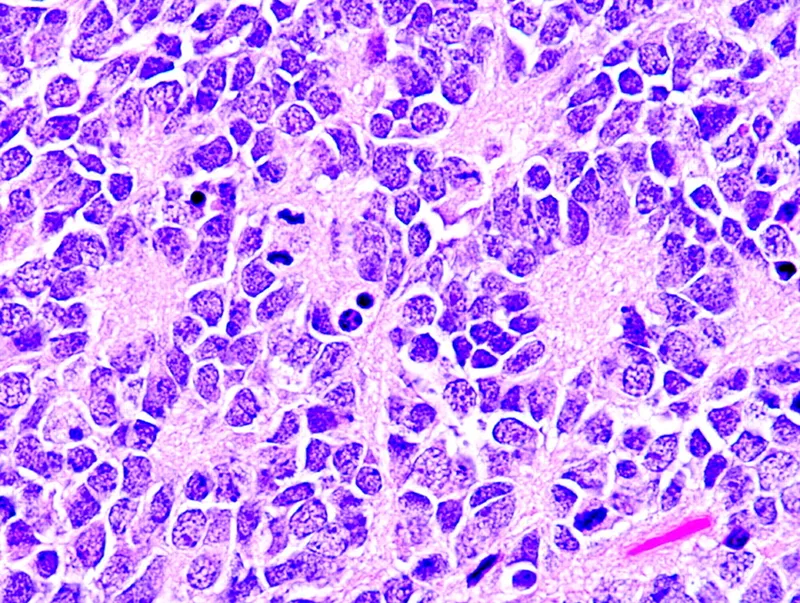

- Diagnosis: ↑ urine VMA/HVA; biopsy shows small, round, blue cells, Homer-Wright pseudorosettes.

- Neuroblastoma: Homer-Wright pseudorosettes on histology; N-myc amplification signifies poor prognosis.

Neuroblastoma - Kiddo's Neural Crest Crisis

- Origin: Neural crest cells (adrenal medulla/sympathetic ganglia).